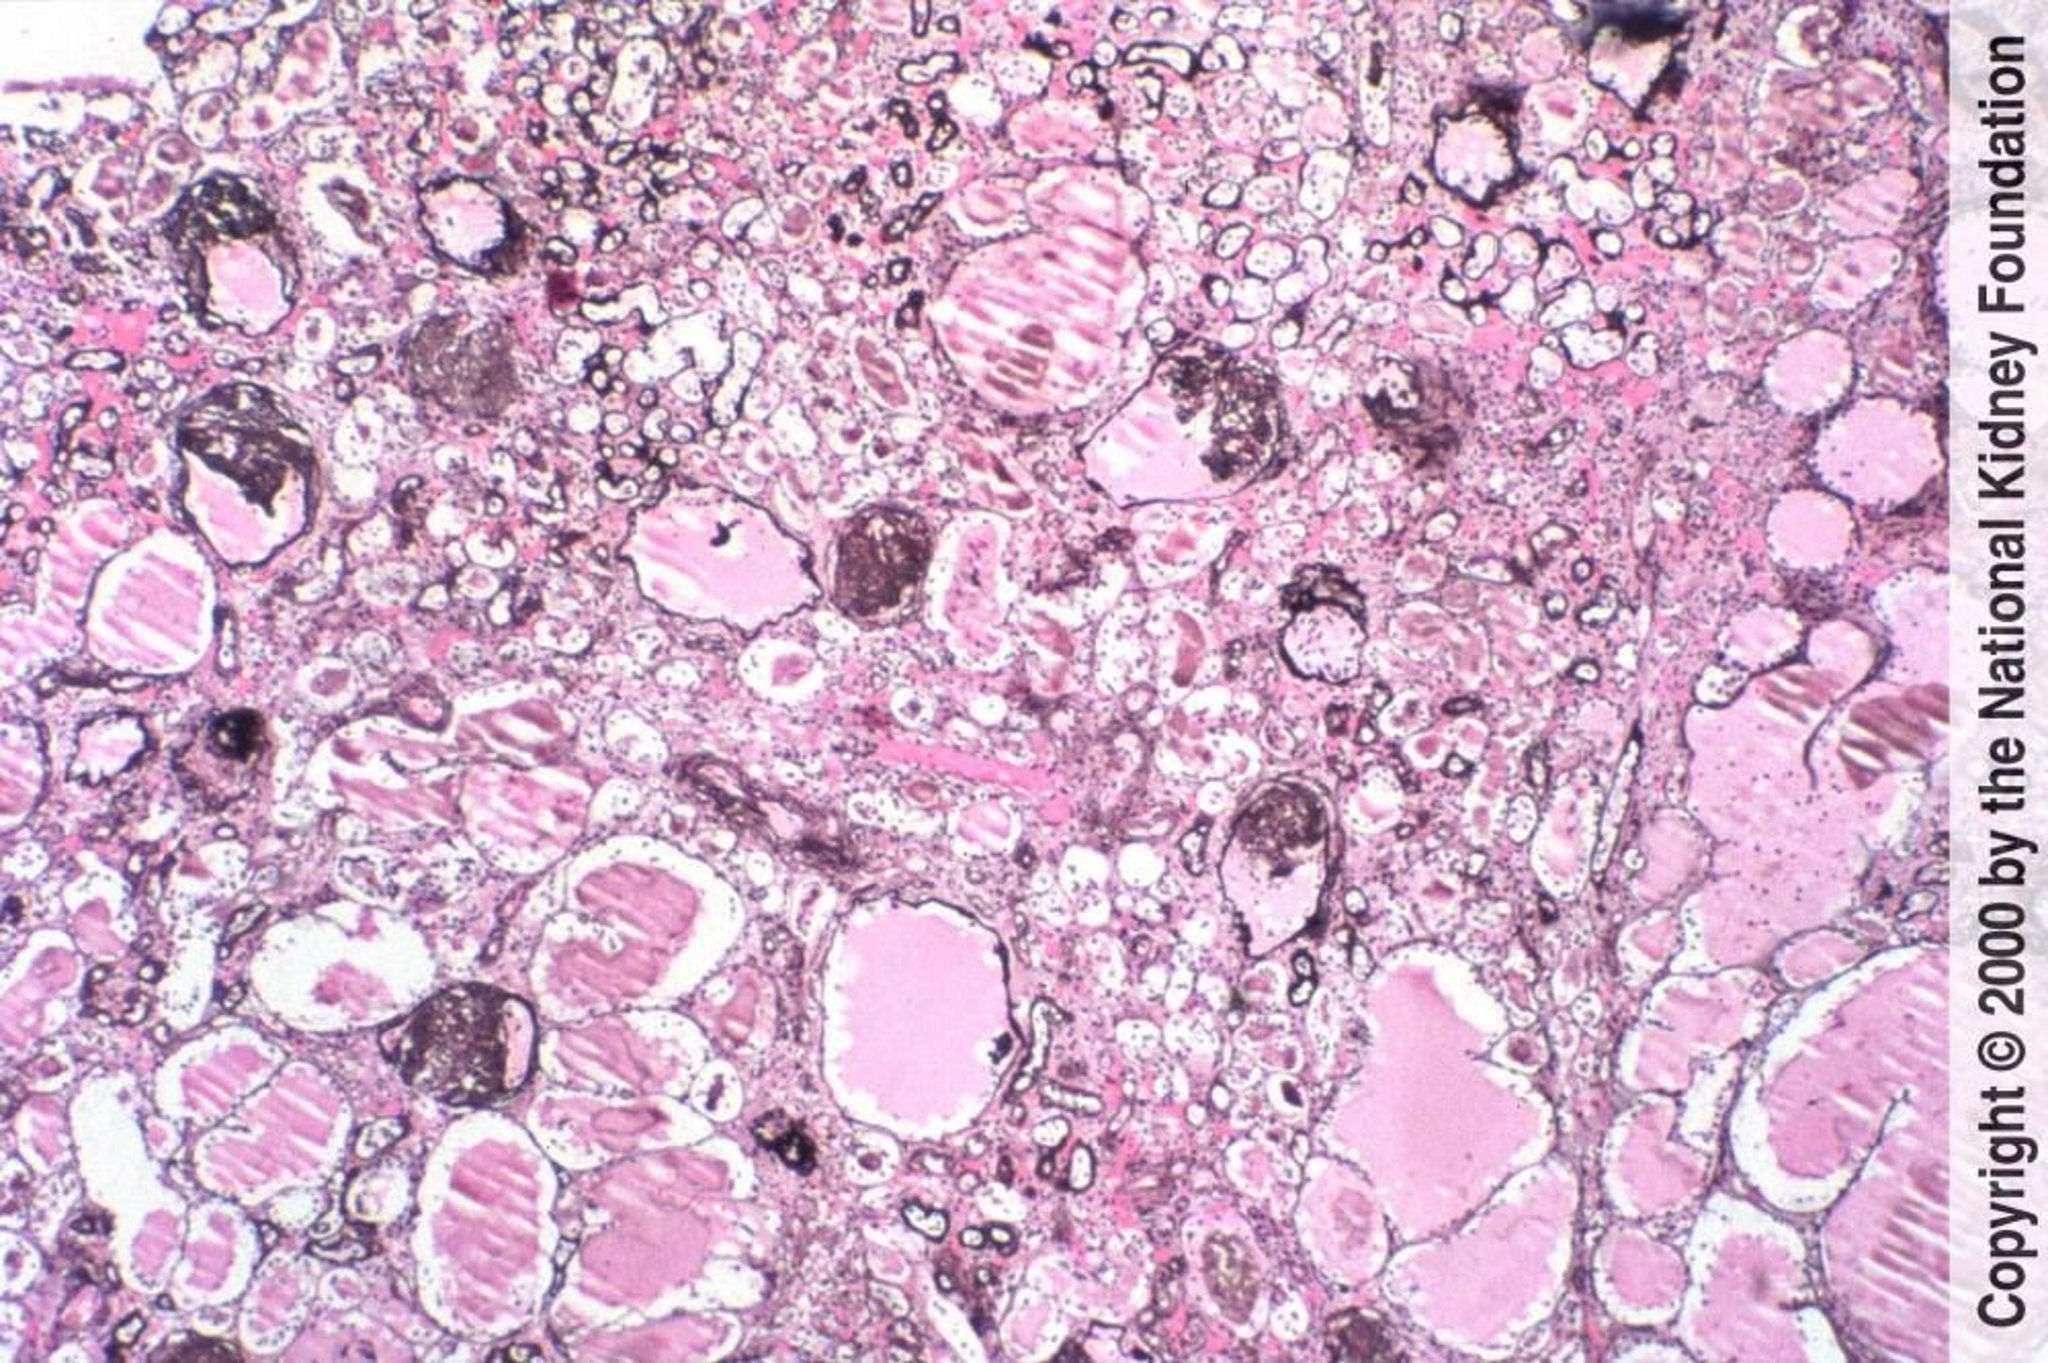

HIV関連腎症(虚脱型糸球体症)

HIV関連腎症の特徴は,糸球体係蹄の虚脱および尿細管の小嚢胞性変化を伴う巣状分節性糸球体硬化症である(PAM染色,100倍)。

Image provided by Agnes Fogo, MD, and the American Journal of Kidney Diseases' Atlas of Renal Pathology (see www.ajkd.org).